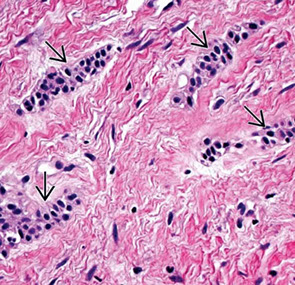

Histology

Submandibular gland

Mixed salivary gland, predominantly serous acini, some mucous acini with serous demilunes

- short intercalated ducts, and striated ducts c simple cuboidal lining epithelium

Parotid gland

Serous salivary gland, serous acini, zymogen granules, intercalated ducts, striated ducts, interlobular ducts c stratified epithelium, lobules c connective tissue septa and nearby LN c capsule